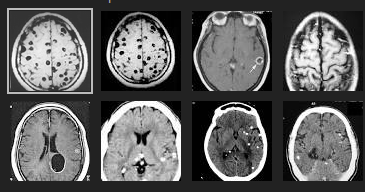

H9

Chụp MRI và CT cho hình ảnh vệt di chuyển và nhiều búi phình mạch nội sọ, chuyển bệnh nhân vào tuyến trên, xác định tác nhân qua ELISA với G. spinigerum dương tính với OD = 2,34, nồng độ IgE tăng gấp 5 lần trị số bình thường. Thuốc lựa chọn albendazol plus dexamethason], bệnh nhân hồi phục hoàn toàn sau 78 ngày điều trị.

·Tuy nhiên, sau 38 giờ kể từ khi nhập viện bệnh nhân mất ý thức à chuyển sang chẩn đoán bệnh do ký sinh trùng, xét nghiệm 6 loại giun sán, kết quả dương tính với G. spinigerum 1/3200

à Chuyển điều trị hồi sức tích cực, chụp CT-scanner cho hình ảnh phù não nhẹ, hình ảnh di chuyển và giống calci hóa tại hai bán cầu. Phác đồ thuốc lựa chọn [albendazole + dexamethason + hydrocortison + kháng sinh phổ rộng], bệnh nhân tỉnh táo sau 14 ngày và hồi phục hoàn toàn sau 5 tháng kể từ khi điều trị.